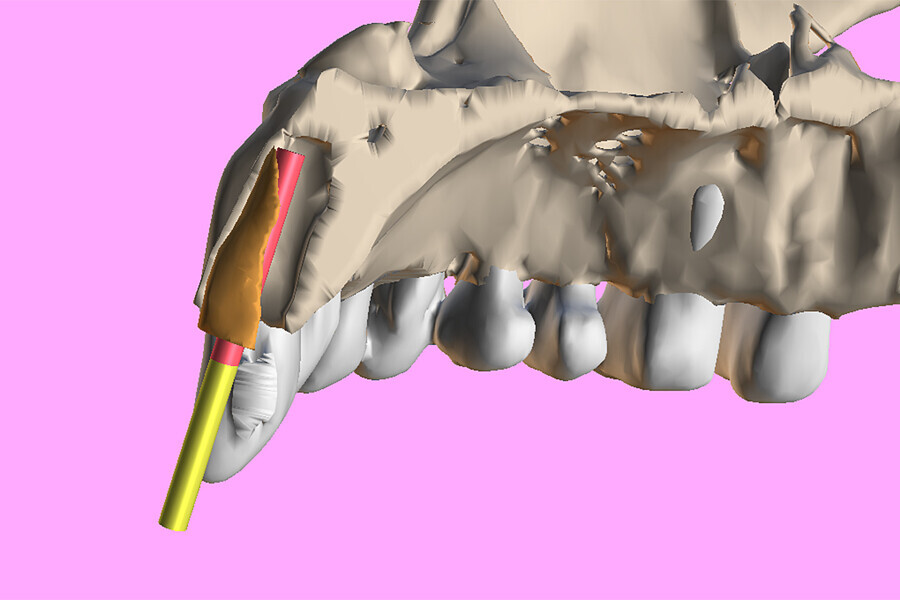

Fig. 3a: Planning the initial drill path using a custom implant design (red) to match the

diameter of the initial drill to reach the tooth apex. The abutment projection is shown in yellow.

3b: The simulated implant within the Triangle of Bone (red), placed to avoid the root fragment seen in yellow (white arrows).